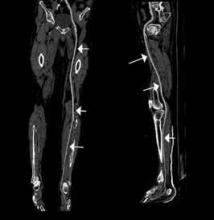

Figure 1. Computed tomography angiography curved multiplanar reformat of the left lower extremity in a patient who suffered leg trauma, multiple fractures, and probable dislocation shows intact main arterial vessels (white arrows) without evidence of pseudoaneurysm.

An emerging clinical situation in which contrast-enhanced cross-sectional imaging may supplant the need for arterial puncture and digital subtraction angiography is multiligament trauma to the knee. When significant kinetic force is applied to the knee, the joint is at risk for translocation and/or dislocation, with resultant injury to the surrounding soft-tissue envelope and potential trauma to the neurovascular structures around the knee. In this type of injury, cross-sectional imaging is routinely ordered to further evaluate and classify trauma, revealing potentially treatment-altering information concerning the integrity of the vascular structures with minimal risk to the patient (Figure 1).